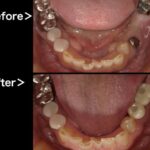

当院の精密根管治療 では、根管治療に精通した日本顕微鏡歯科学会認定医が十分な時間をかけて診療しております。また、様々な機器、薬剤を用いて、患者様の大切な歯をできる限り残すための環境を整えております。

マイクロスコープで視野を拡大することで、肉眼では見つけにくい病変を適切に処理し、治療箇所を長持ちさせるように心がけています。

当院では必要に応じて、保険診療であってもマイクロスコープを使って根管治療を行います。視野を拡大した細かい作業のため時間はかかりますが、再発を抑えて長期的にご自身の歯を使用できるような治療を心がけております。